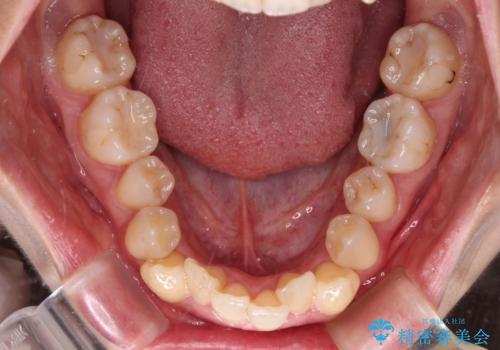

【モニター】急速拡大装置 狭い歯列を拡大してワイヤー装置で短期間治療

1. 開始前

1. 【モニター】急速拡大装置 狭い歯列を拡大してワイヤー装置で短期間治療の治療前